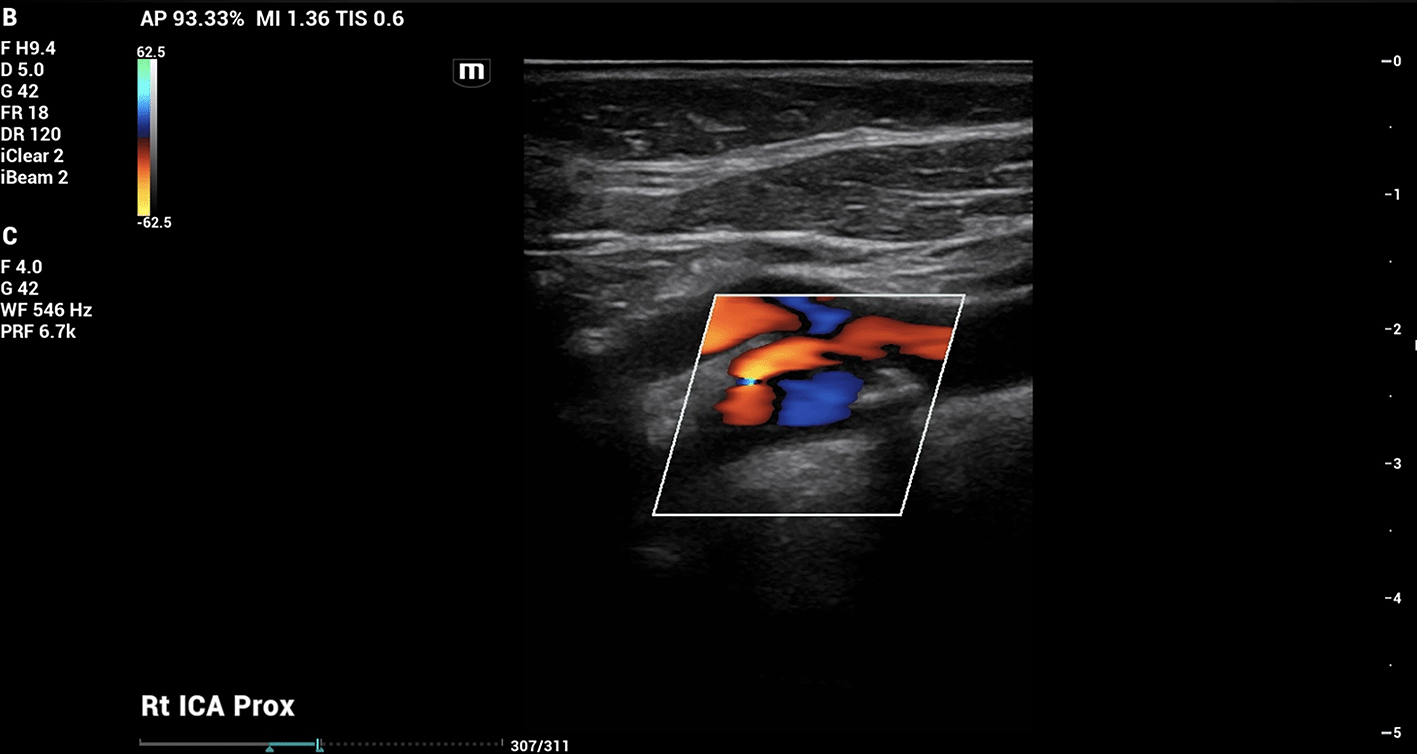

On doppler imaging study, all vessel velocities measured by carotid duplex were significantly higher on the right side than the left. The measured peak velocity of the right internal carotid artery (ICA) was 122.02 cm/s, the external carotid artery (ECA) 118.45 cm/s, and the common carotid artery (CCA) 98.81 cm/s. The left sided measured peak velocities were the ICA of 47.33 cm/s, the ECA of 75.59 cm/s, and the CCA of 68.88 cm/s. In addition, the vessel velocity difference was greater in the ICA at 74.69 cm/s, than in the ECA (42.86 cm/s) or the CCA (29.93 cm/s). The carotid duplex interpretation concluded 50% stenosis in the right ICA ( Figure 1) with heterogenous calcified plaquing and minimal stenosis on the left. The patient was therefore referred for further vascular evaluation.

Figure 1. Carotid doppler imaging.

Carotid doppler showed 50% stenosis in right carotid bulb and proximal cervical internal carotid artery (ICA).